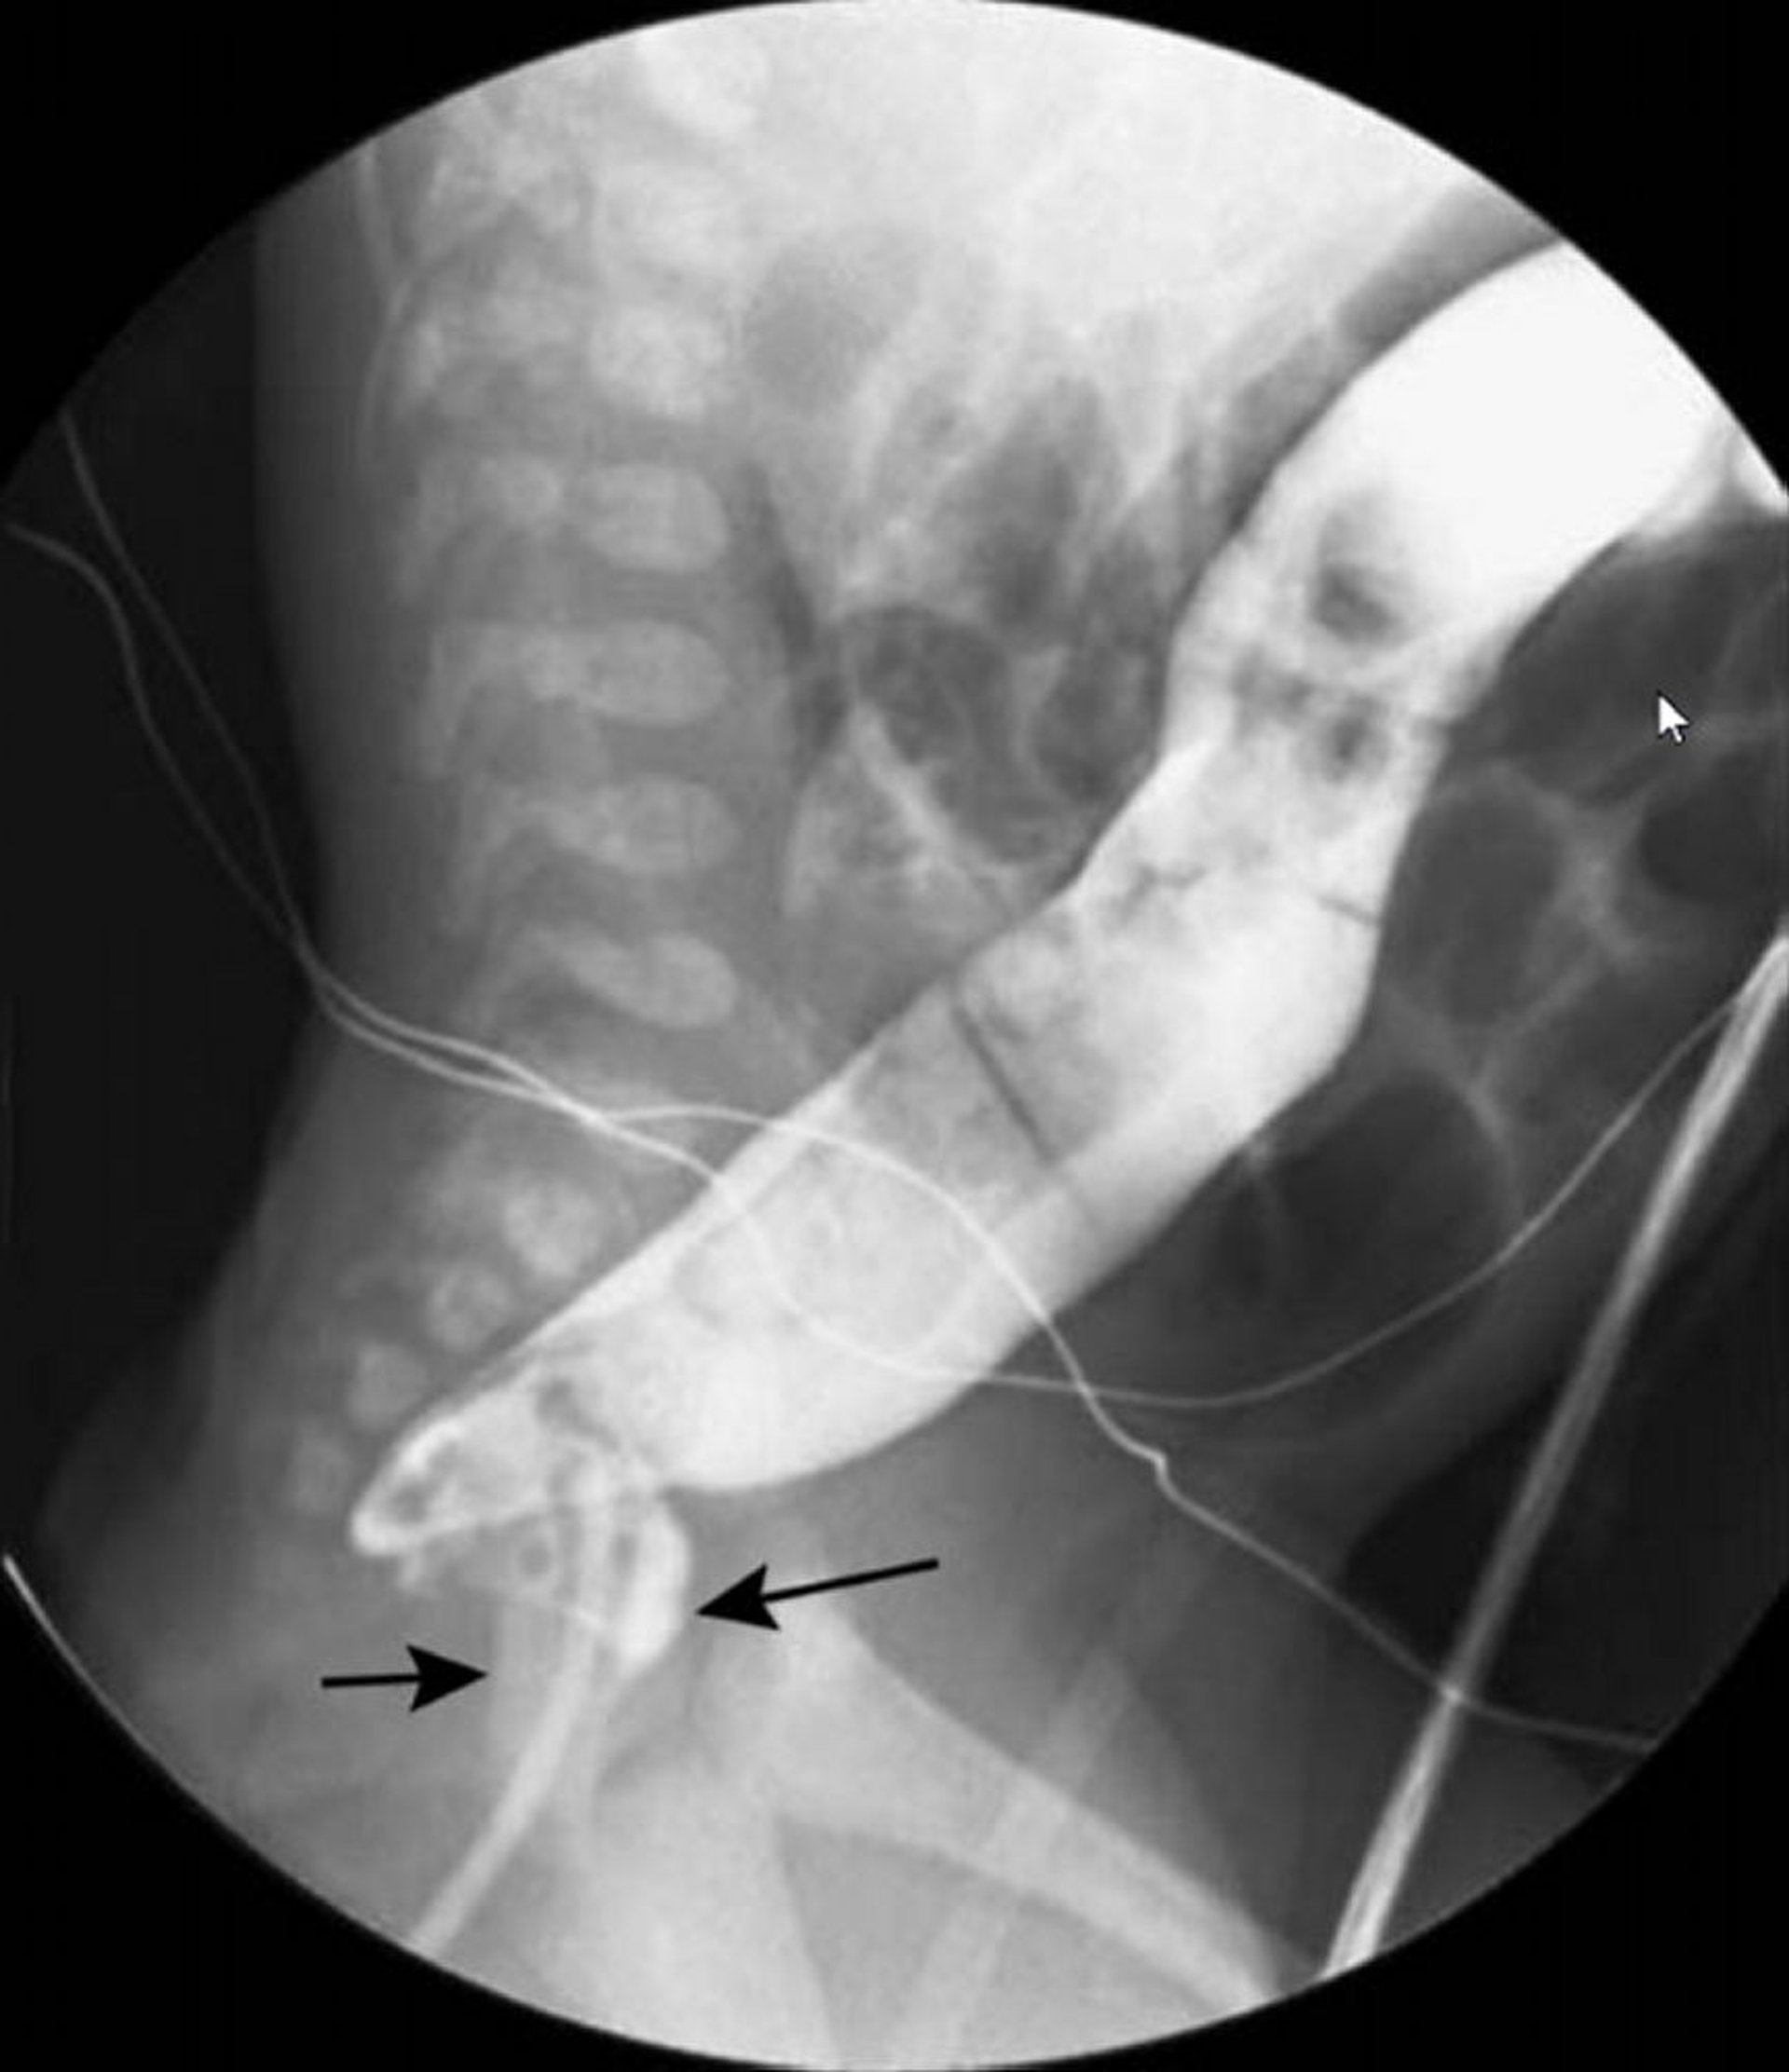

Clisma opaco a contrasto singolo che mostra l'aspetto a collo di cigno della malattia di Hirschsprung

In questa immagine, il clisma opaco mostra un retto ristretto (frecce nere) e un colon dilatato (freccia bianca) più prossimalmente.